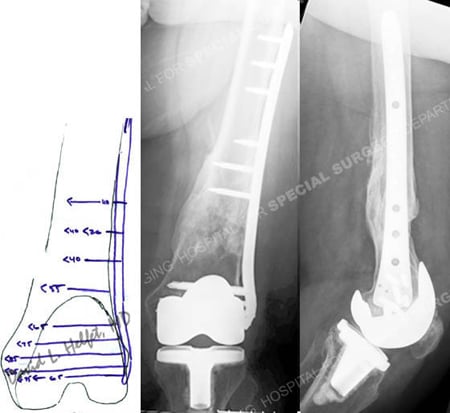

preoperative plan and radiographs 2 years following fracture surgery from a case example of periprosthetic femur fractures from the orthopedic trauma service at Hospital for Special Surgery.

Pre-operative plan (left image) for fracture reduction and fixation with a LISS locking plate and anteroposterior and lateral views at 2 years (right images) following fracture surgery illustrate a healed periprosthetic femur fracture.